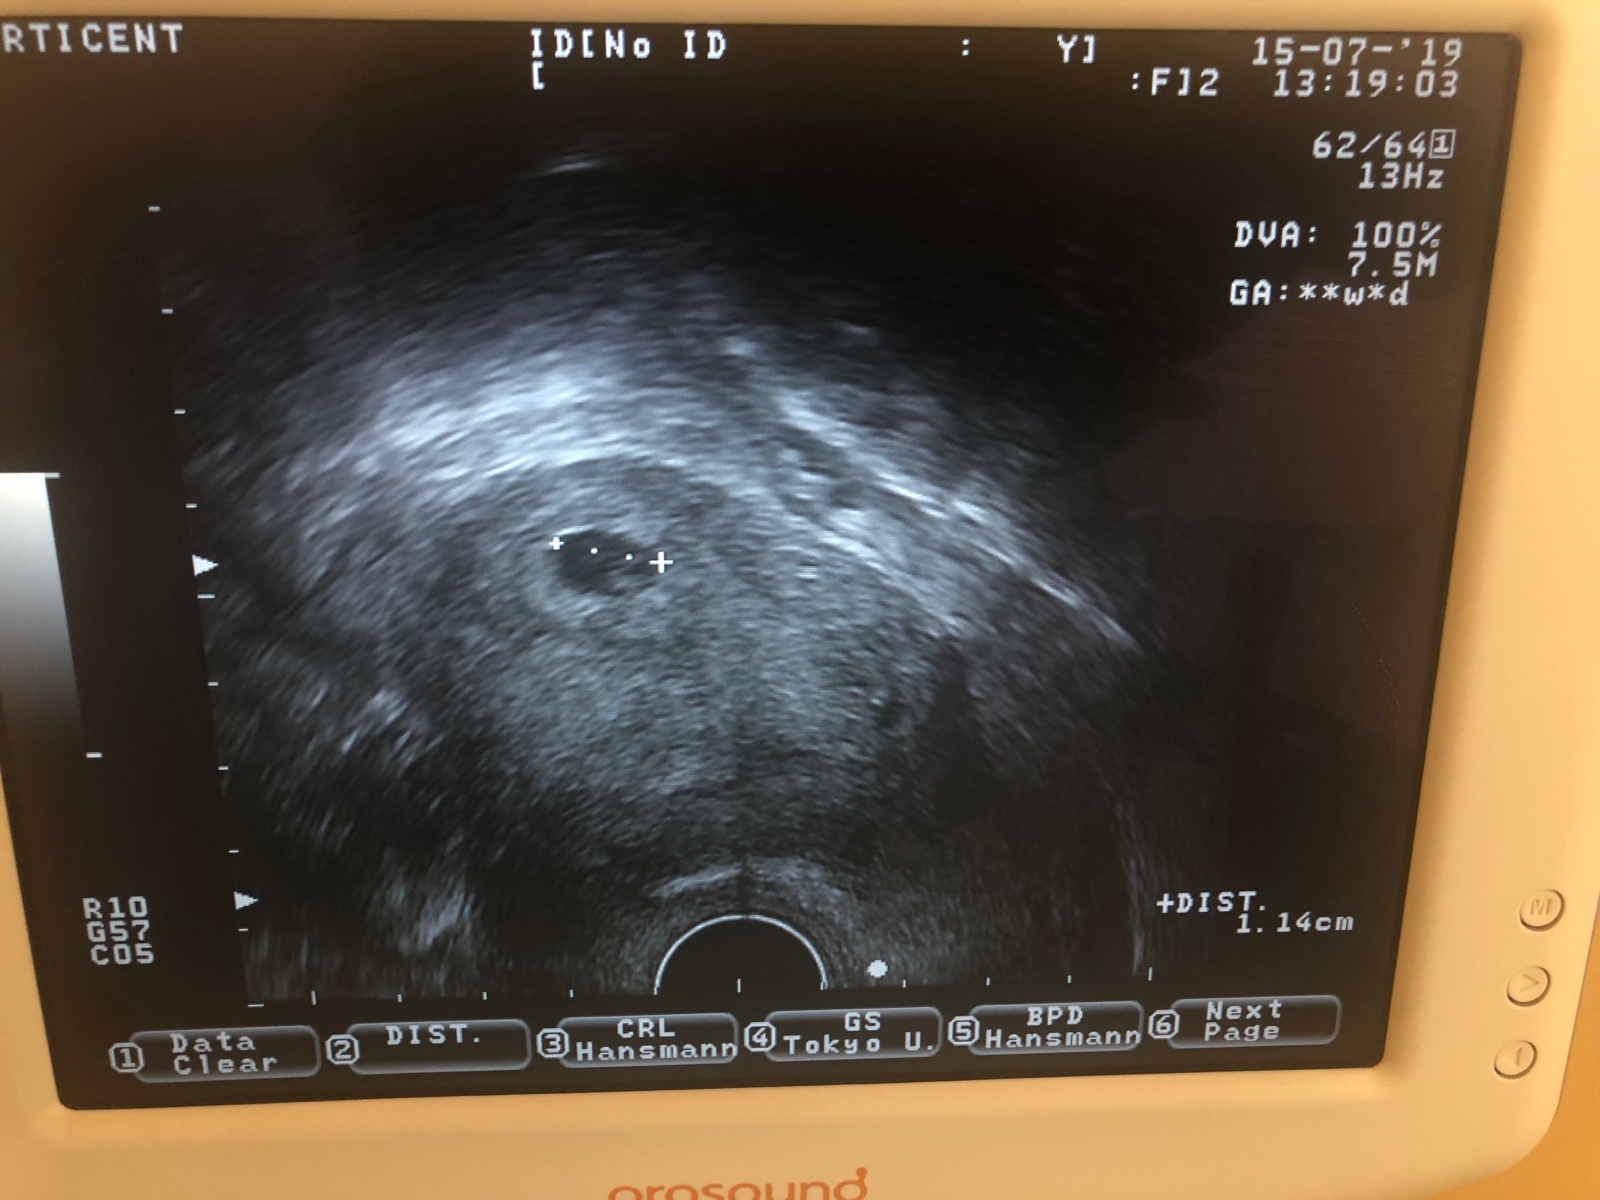

@fialka1318 ja neviem mám nejaké zmiešané pocity. Povedané mi bolo že vidím gastracny vak mal 1.2cm . A že aj bije srdiečko . Takú bodku ukazoval . A to je všetko . Že zas o dva týždne 🤷🏻♀️. Ja neviem teda . Ale takto skoro čo som mohla čakať že ...

@evulik1111 a neokecal ti normalne ze co a ako? Ani embryjko neodmeral v ktorom je tyzdni nic? Ani sono ti nevytlacil fotku? Tak to nejak odflakol :-O namiesto toho aby ti ako tehulke pekne vsetko povedal a ta potesil ta len stresuje :-O hm tak neboj urcite je vsetko ok 🙂 malinkemu bije srdiecko tak na nic ine ani nemysli 🙂 a mozno su tam dve 🙂 to by asi este nebolo vidno ci? 🙂 ale dole vpravo mas malinke embryjko tak urcite je velke 😉 a aj zdravucke :-* na nic ine ani nemysli a tes sa na dalsie sono kde uz bude vidno aj rucky malinke a nozky 😉 ja idem buduci tyzden tak tiez verim ze bude vsetko ok 😉 a na dalsi den opat k svojmu aby ma potesil znova 😉 poradil mi nejakr vitaminy a ze ich kludne mozem jest tak idem do toho 😀 hlavne nech ma vsetky vitaminy a je zdravunke 😉